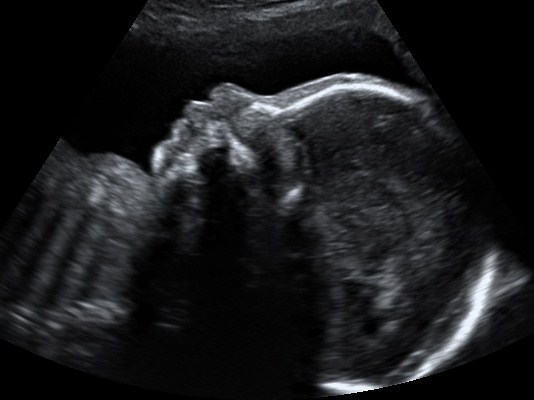

Under the guidance of qualified Sonography Instructors, enrolled HGTC Ultrasound students will perform these ultrasounds to refine their scanning skills while providing families with cherished images of their newest addition. These one-hour sessions offer expectant mothers and their loved ones a chance to witness their baby's development firsthand, all while contributing to the education of future healthcare professionals.

"We are thrilled to provide this invaluable opportunity for expectant mothers in our community," said Susan Gallant, Professor and Clinical Coordinator of Diagnostic Medical Sonography at HGTC. "Not only does this program allow our students to gain real-world experience, but it also gives families a memorable glimpse into their baby's journey."